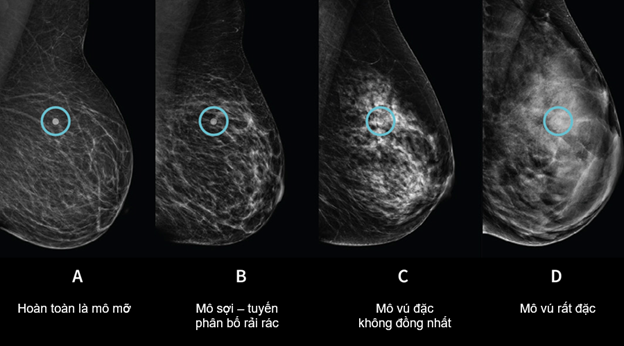

Trong thực hành lâm sàng, mật độ mô vú là yếu tố có thể ảnh hưởng đáng kể đến độ nhạy của nhũ ảnh. Ước tính khoảng 40 -50% phụ nữ có mô vú đặc (mật độ loại C và D theo BI-RADS), độ nhạy của nhũ ảnh giảm sút nghiêm trọng.

“Trắng chồng trắng” là cách nói dễ hiểu cho hiện tượng: mô tuyến vú đặc và khối u đều hiện trắng trên phim, tạo nên hiệu ứng che lấp (masking effect), khiến tổn thương có thể bị bỏ sót dù vẫn nằm trong trường quan sát.

Hình 1. Mô vú càng đặc, khả năng 'tàng hình' của khối u trên nhũ ảnh càng cao